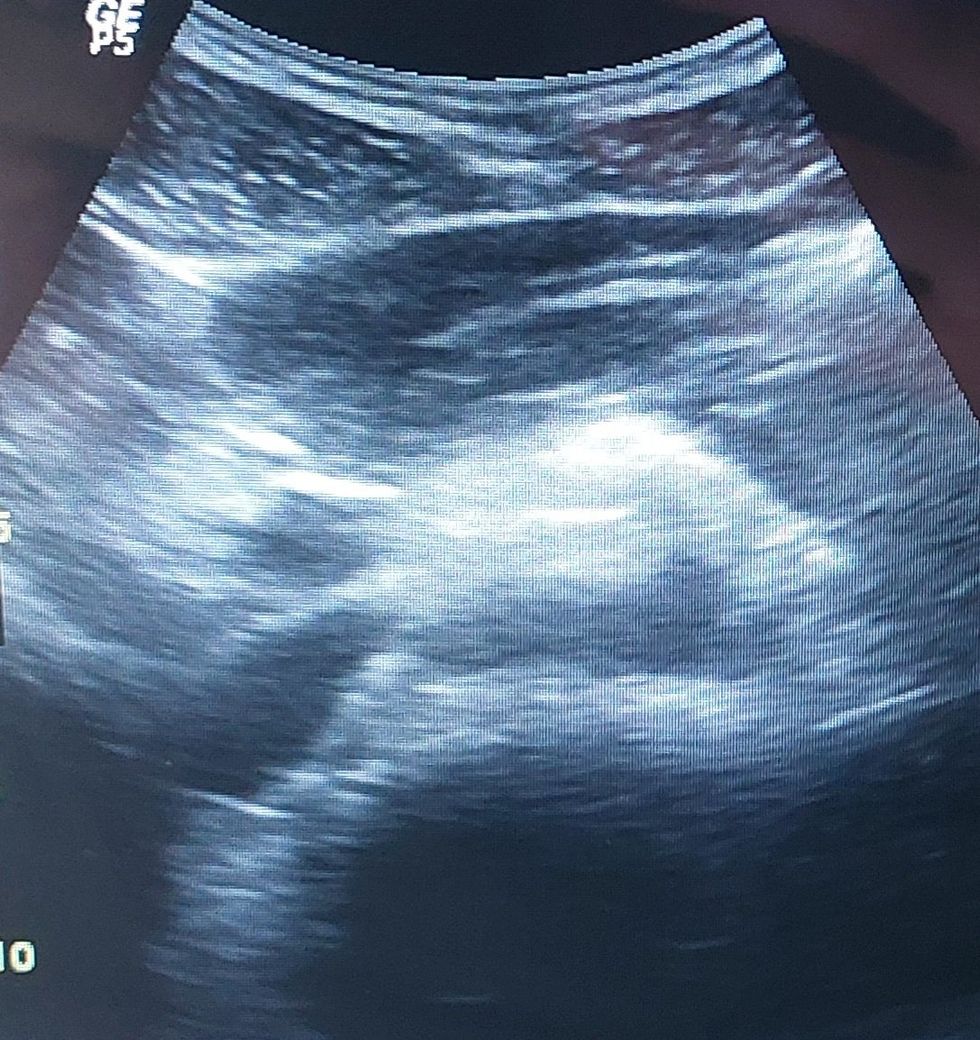

동네내과에서 복부초음파를 했었는데요 사진을 봐주시면 감사하겠습니다 정상이라고 분명히 들어서요 췌장도 정상이라고 들어서요 췌장도 잘보인다고 들었습니다. 사진올렸으니 봐주시면 합니다.

초음파는 연속적인 모습을 보기 때문에 하나의 사진으로 췌장 전체를 확인하지는

못하지만 특별히 췌장 주변에 종양이나 이상을 보이지는 않는 것으로 보입니다.

뒷쪽의 하얀 부분은 혈관과 함께 장이 관찰되는 것으로 보입니다.